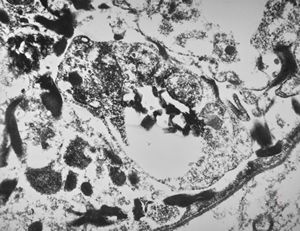

F,50y. | progressive multifocal leukoencephalopathy- viral particles in a glial cell

F,50y. | progressive multifocal leukoencephalopathy- viral particles in a glial cell

F,50y. | progressive multifocal leukoencephalopathy- viral particles in a glial cell